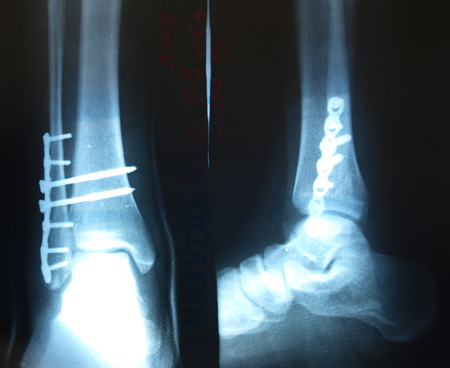

Прямоугольную длинную пластинку поставили на кость, из какой-то дорогущей шведской стали. На семь саморезов. У меня смещения-то не было, лёгкий перелом. Проблема в оторвавшихся связках - их и прикрепили пластинкой. Снимать в октябре-ноябре будут.

Чтобы наглядней было, что было у Тимсона)

Вложения:

000efytp.jpeg

000efytp.jpeg [ 116.72 КБ | Просмотров: 1197 ]